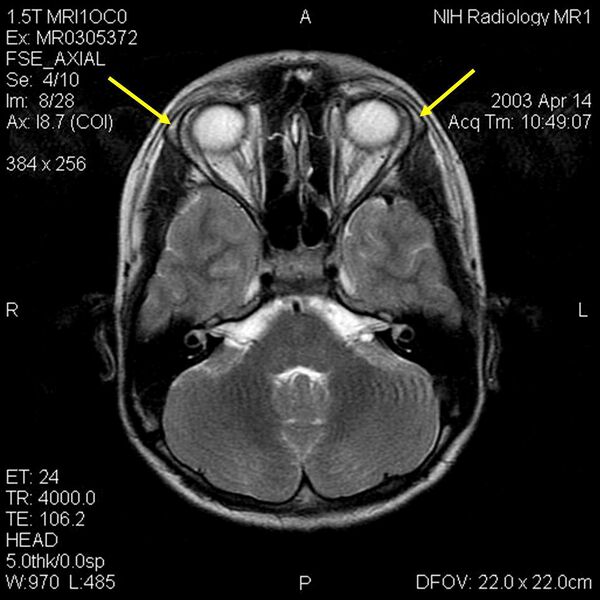

Лица, пострадавшие от ААА, имеют надпочечниковую недостаточность/болезнь Аддисона из-за сопротивления ACTH, алакримию (отсутствие слезной секреции), и ахалазию (отказ кольца мышечных волокон, такого как сфинктер) нижнего пищеводного (кардиального) сфинктера, который задерживает грудного отдела пищевода. При этом признаками вегетативной дисфункции с ААА также могут быть такие, как аномалии зрачка, ненормальная реакция на внутрикожный гистамин, нарушение потоотделения, ортостатическая гипотензия и нарушения сердечного ритма[5]. Гипогликемия (низкий уровень сахара в крови), часто упоминается в качестве раннего признака[4]. Это расстройство также было связано с мягкой умственной отсталостью[4].